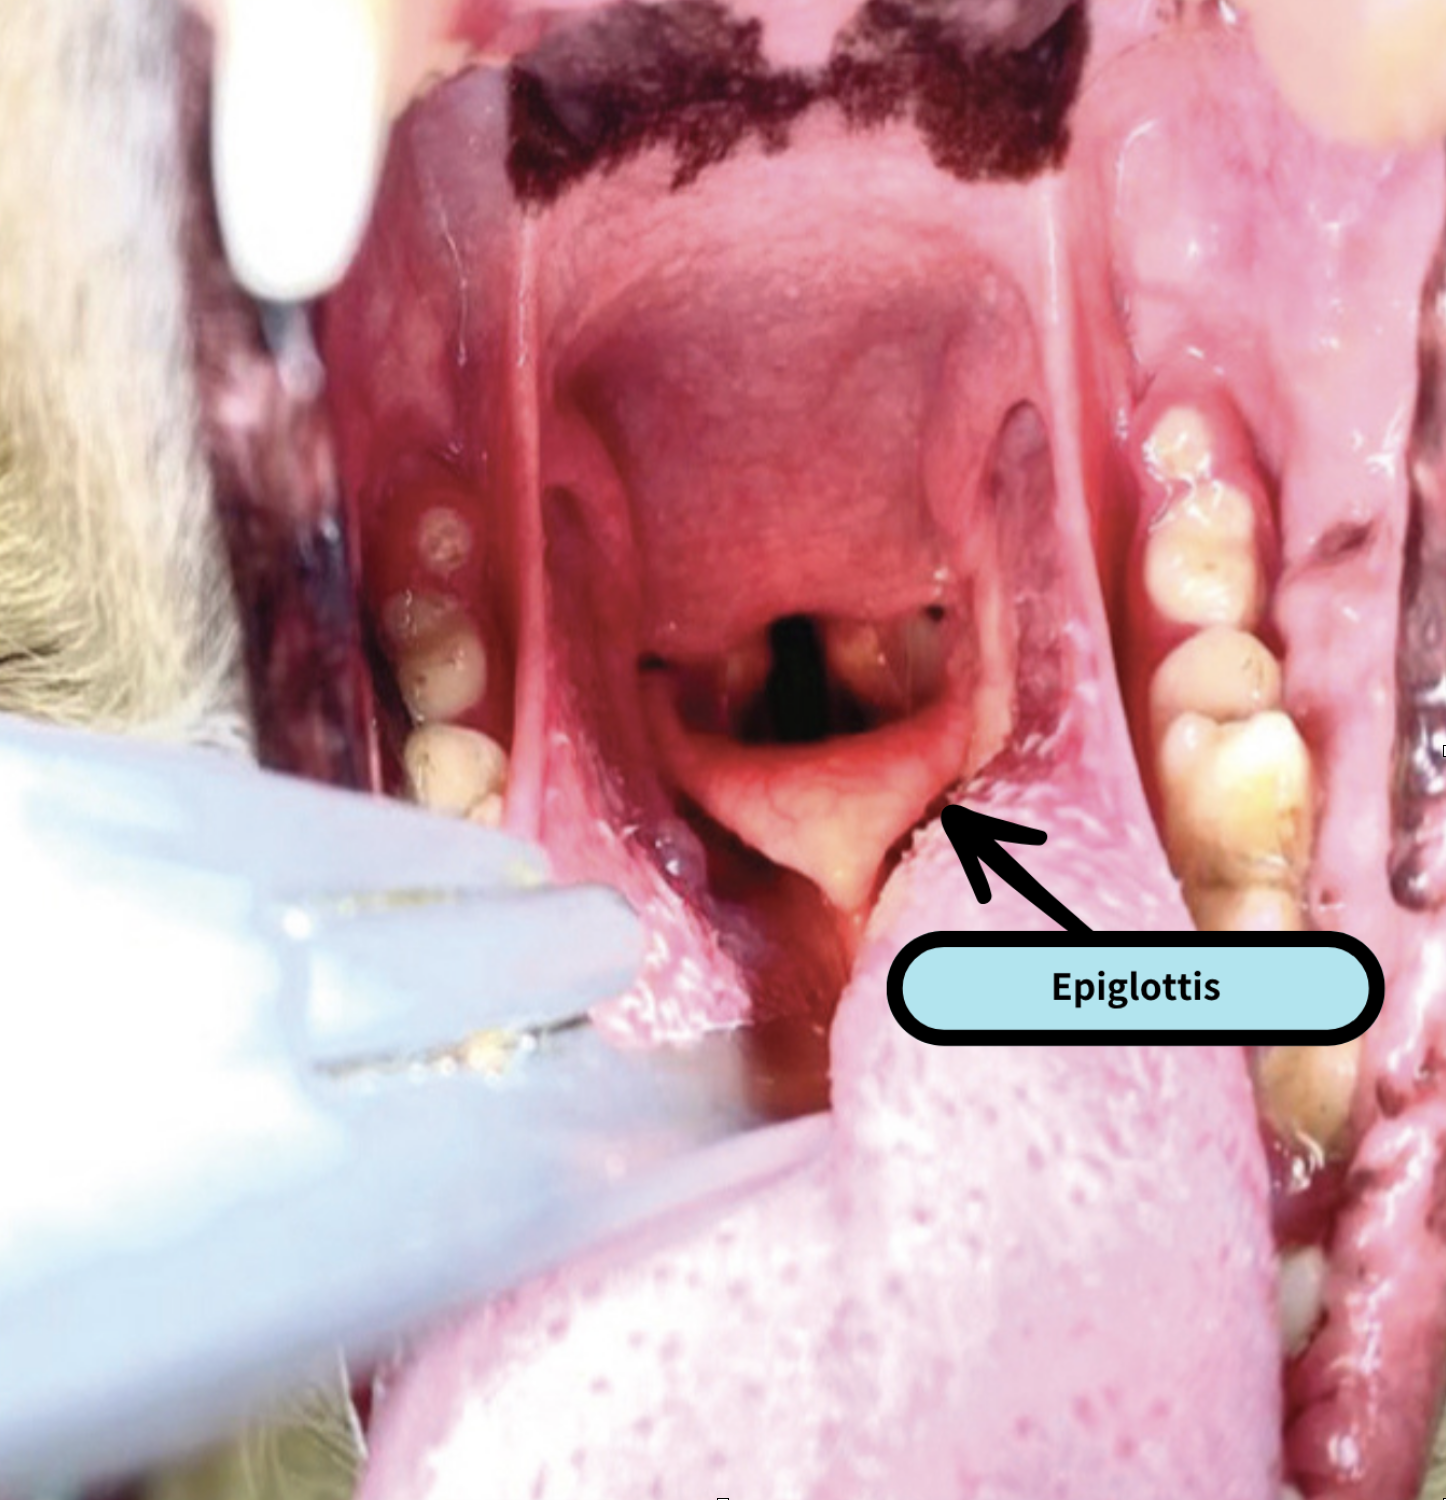

使用喉鏡有助於可視化會厭(Epiglottis),特別適合初學者,但喉鏡切勿放得太入而直接壓到會厭,應壓舌根使會厭自然下垂。